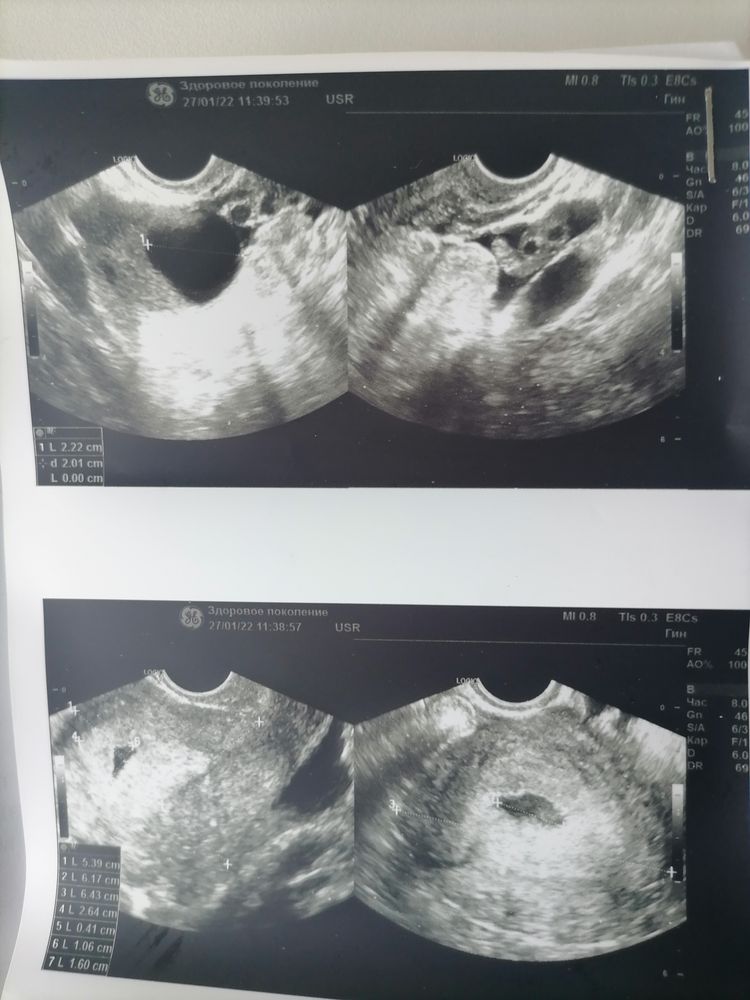

Узи ставят 5 недель

Сходила на узи говорит матка на 5 недель, а плода нету

Никого не смущает кровь под ? Полости матки?я соглашусь скорее с автором..надо 1. К врачу 2 узи в динамике через неделю